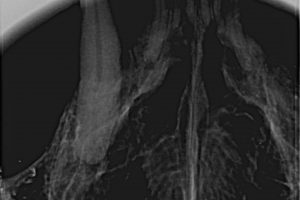

Vom Unterkieferdolchzahn dieser Katze war einfach nur die Krone weggebrochen. Die Wurzeln mitsamt den Nerven waren im Knochen steckengeblieben. Sowas tut wirklich furchtbar weh.